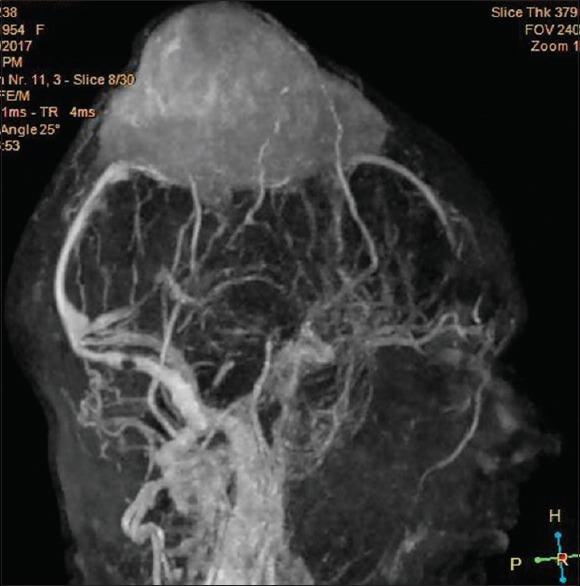

Plasmacytomas occur as lesions in soft tissue or bone. Skull vault plasmacytomas are rare lesions comprising 0.7% of all plasmacytomas. Workup for myeloma must be done in such cases to rule out multiple myeloma. Here, we report a case of a 63-year-old female who presented to us with a large skull vault swelling which appeared to mimic a parasagittal meningioma on imaging. Histopathological imaging revealed it to be a plasmacytoma. A retrospective review of the radiology revealed the characteristic "mini-brain appearance" in our case. Literature on the subject is also reviewed.

浆细胞瘤可表现为软组织或骨的病变。颅骨穹窿浆细胞瘤是罕见病变,占所有浆细胞瘤的0.7%。此类病例必须进行骨髓瘤检查以排除多发性骨髓瘤。在此,我们报告一例63岁女性,她因颅骨穹窿部巨大肿胀前来就诊,影像学检查显示其似乎类似矢状窦旁脑膜瘤。组织病理学检查显示为浆细胞瘤。对该病例的放射学回顾显示出其特征性的“迷你脑外观”。本文还对该主题的文献进行了综述。